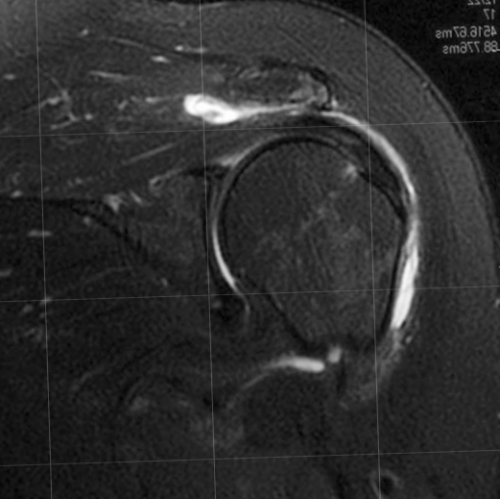

ротаторной манжеты нижней головой (например броски, игра в теннис, волейбол, тяжелая атлетика, плавание и др.).жизни.Патологию ротаторной манжеты